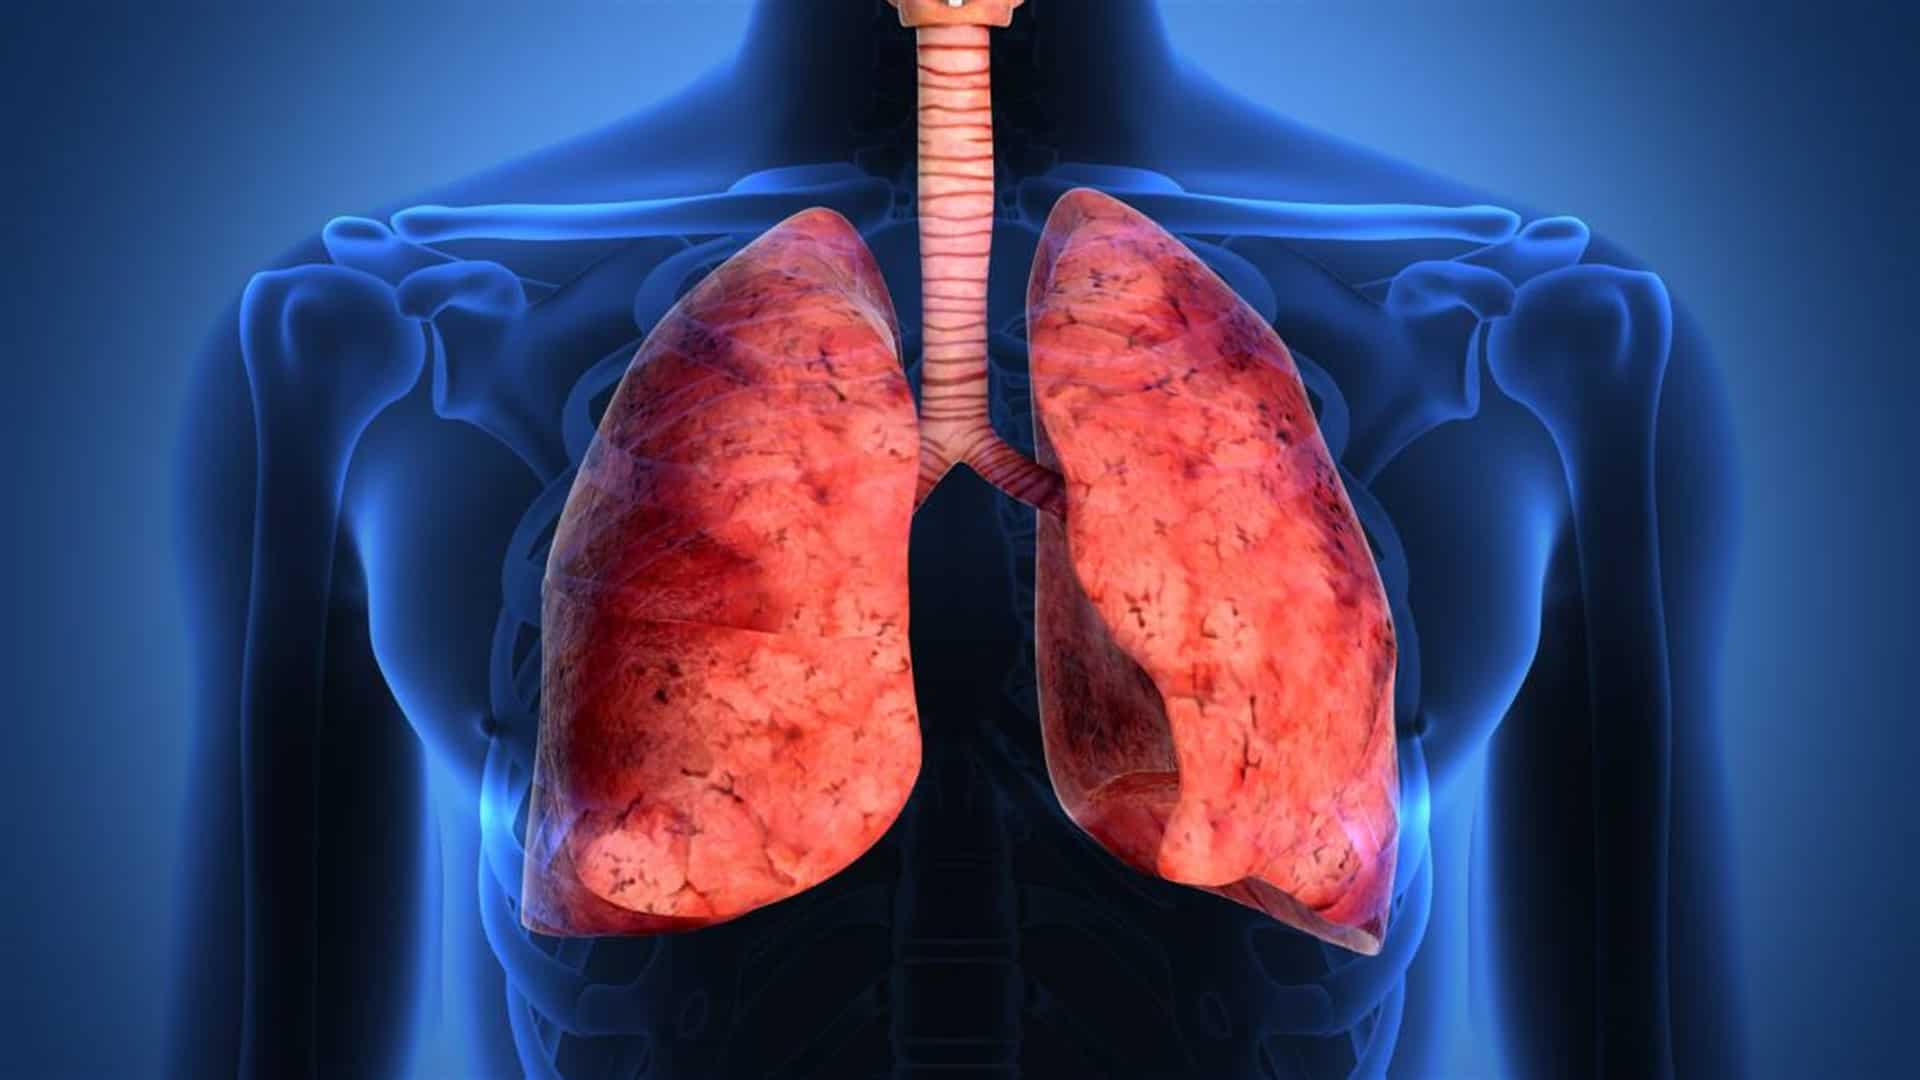

Una entidad que se puede presentar y llegar a ser mortal, es la lesión o edema pulmonar agudo secundaria a la transfusión de hemoderivados -tejido que se deriva o separa a partir de la sangre-, señaló el médico José Luis Campos.

Guadalajara, Jal.- Además de incompatibilidad y otras complicaciones, una entidad que se puede presentar y llegar a ser mortal, es la lesión o edema pulmonar agudo secundaria a la transfusión de hemoderivados -tejido que se deriva o separa a partir de la sangre-, señaló el médico José Luis Campos.

El anestesiólogo adscrito al Hospital de Ginecoobstetricia del Instituto Mexicano del Seguro Social (IMSS) en Jalisco, explicó que se trata de una condición que puede derivar en mortalidad del paciente si se presenta con severidad.

“En ocasiones, muestran sólo datos de dificultad respiratoria, pero en otros insuficiencia y el paciente puede morir”, refirió el especialista, quien añadió que los efectos pueden llegar a presentarse en el rango de seis horas después de la transfusión de plasma y plaquetas concretamente.

Detalló que las causas más frecuentes son inmunológicas, debido a una reacción que se genera derivado de los anticuerpos de los hemoderivados del donante y que presentan incompatibilidad con el receptor. Otra situación es que la vigencia de los hemoderivados que no debe ser mayor a 15 días, lo cual es recomendado para su utilización.

El especialista del IMSS indicó que la lesión pulmonar post-transfusión es una importante causa de muerte del paciente. Reconoció el esfuerzo que realizan los Bancos de Sangre por prevenir esta y otras condiciones adversas asociadas a las transfusiones sanguíneas y de sus hemoderivados.